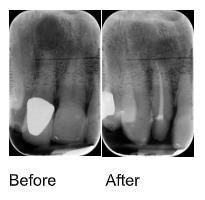

Treatment Results

Before & After X-rays

View examples of successful endodontic treatments demonstrating the precision and effectiveness of our root canal therapy.